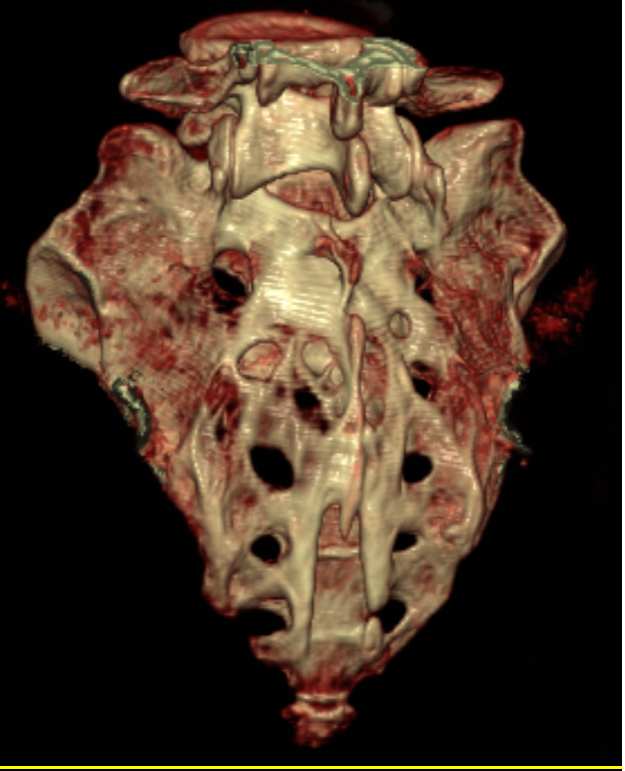

(CT三维重建)